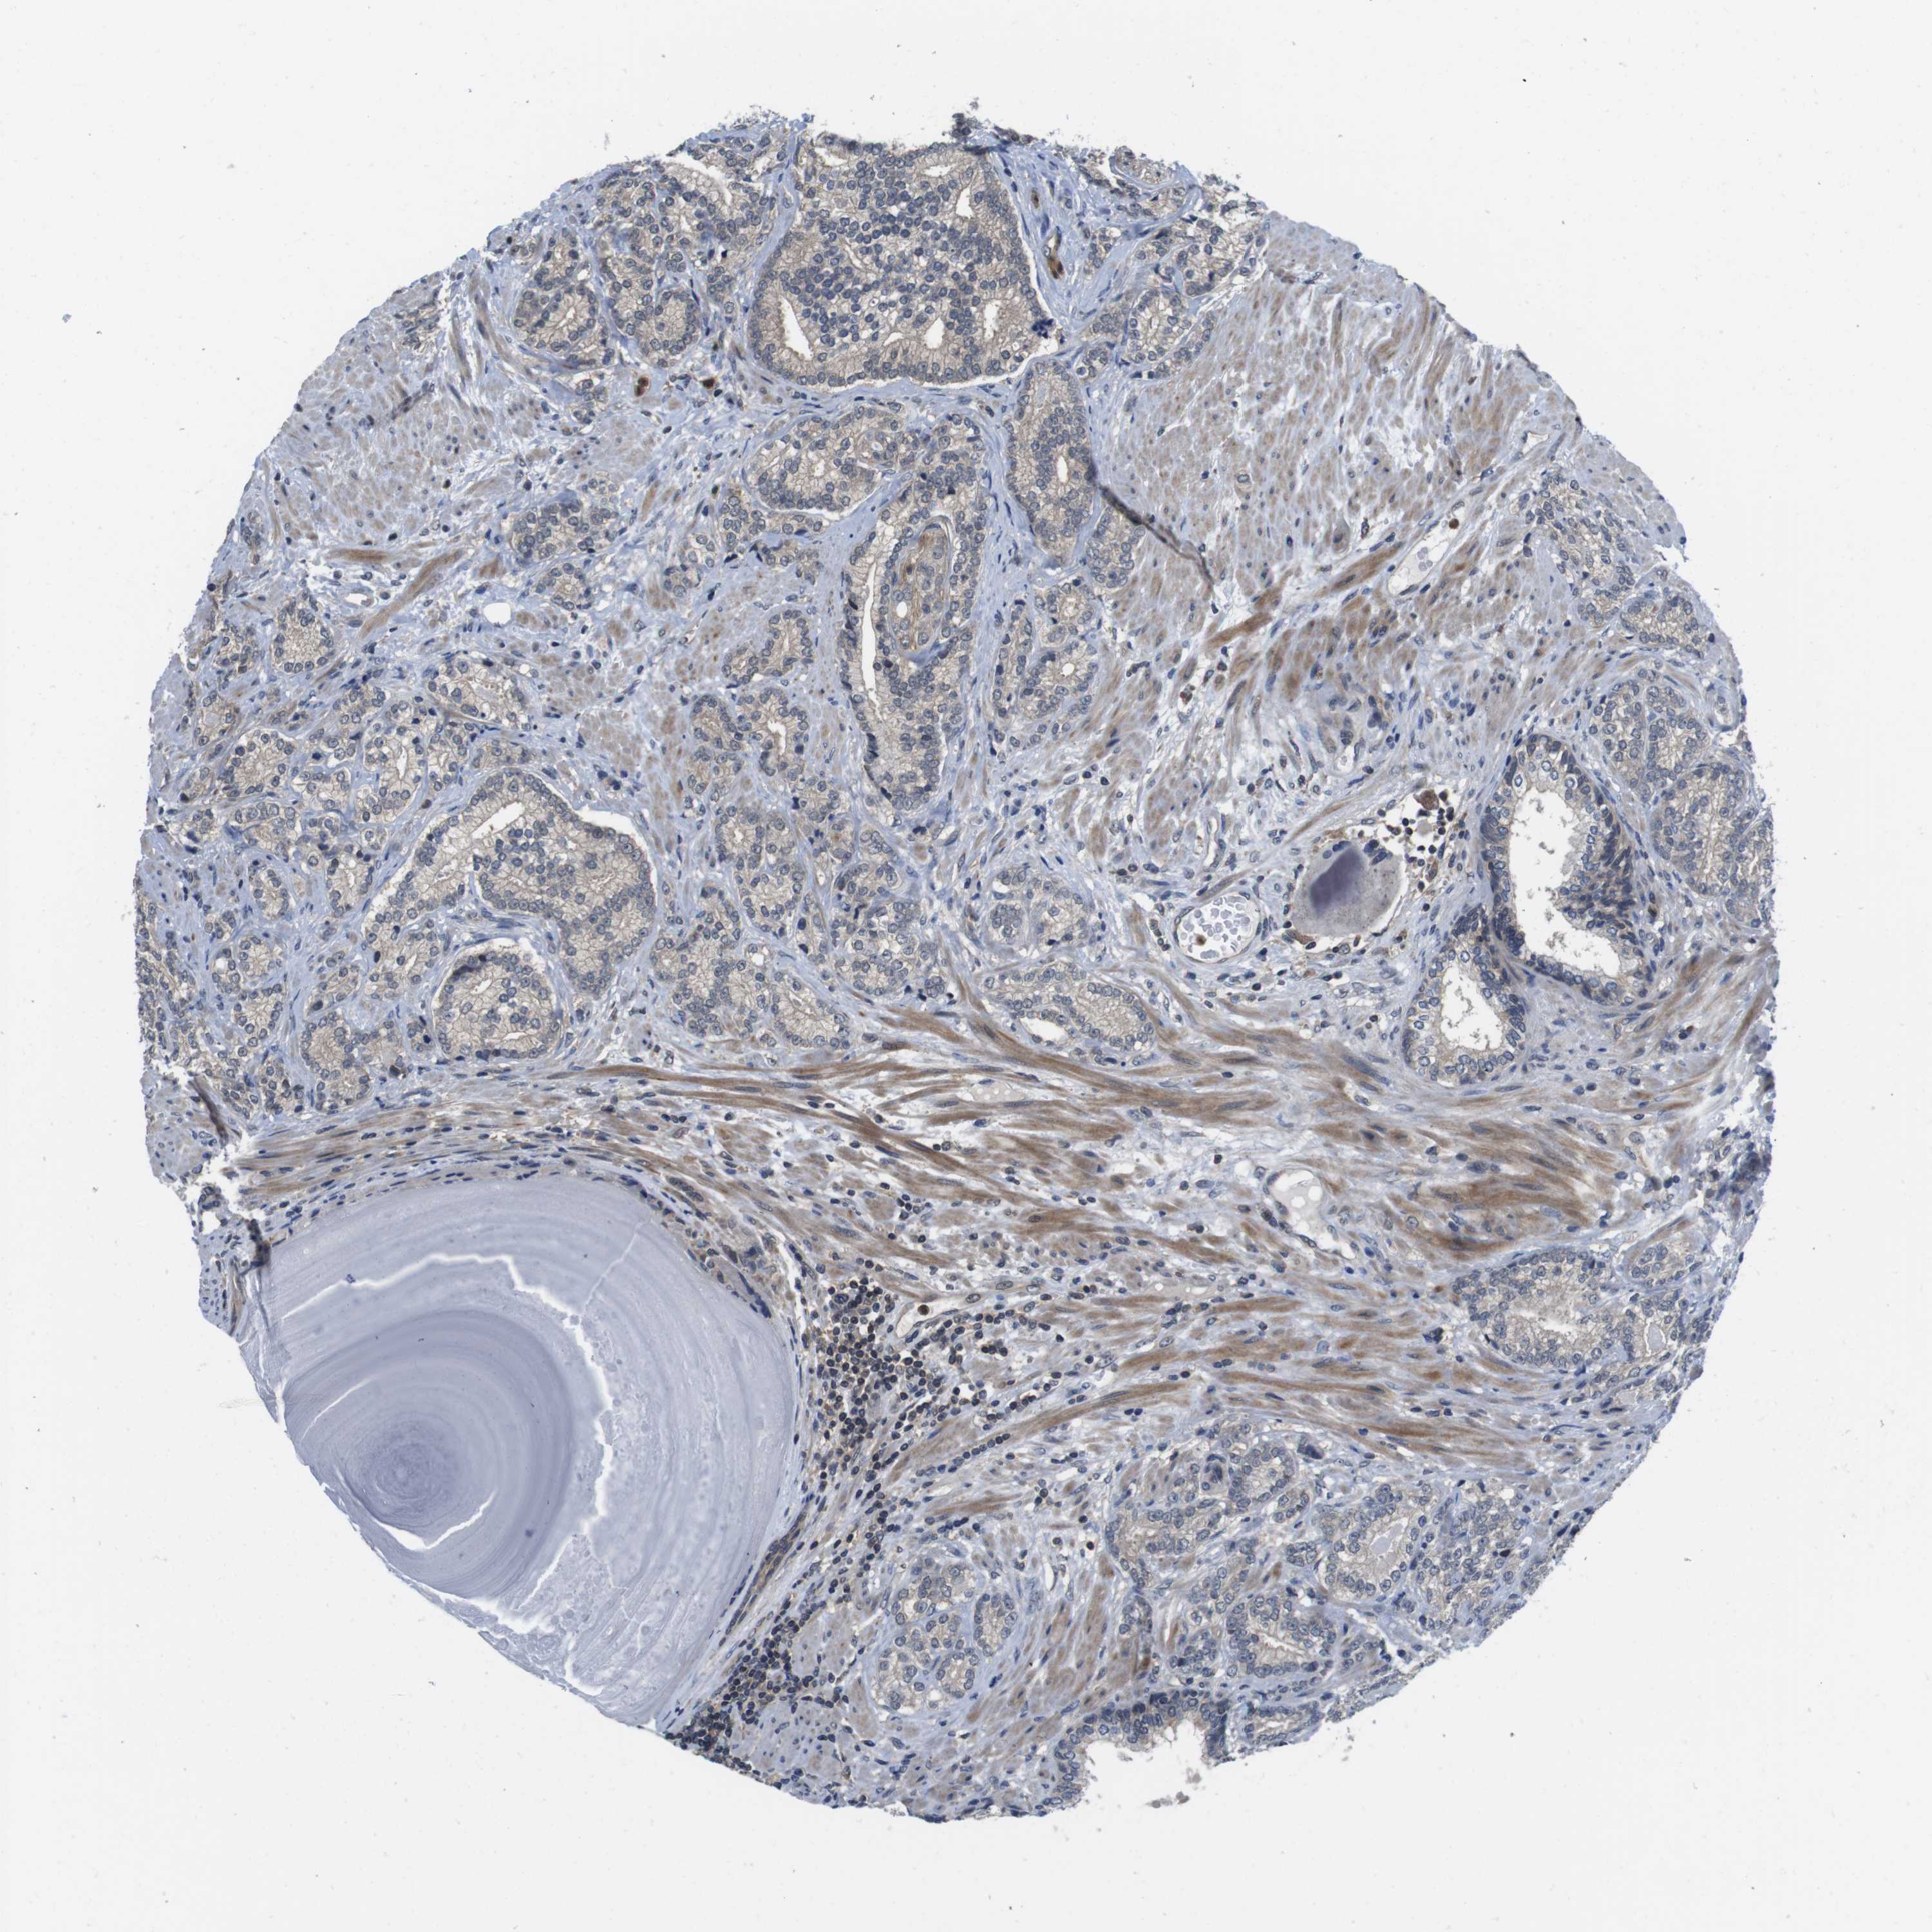

PROSTATE CANCER - Protein expressioni

A mouse-over function shows sample information and annotation data. Click on an image to view it in a full screen mode. Samples can be filtered based on level of antibody staining by selecting one or several of the following categories: high, medium, low and not detected. The assay and annotation is described here.

Note that samples used for immunohistochemistry by the Human Protein Atlas do not correspond to samples in the TCGA dataset.

Antibody stainingi

Antibody staining in the annotated cell types in the current human tissue is reported as not detected, low, medium, or high, based on conventional immunohistochemistry profiling in selected tissues. This score is based on the combination of the staining intensity and fraction of stained cells.

Each image is clickable and will lead to virtual microscopy that enables deeper exploration of all samples and also displays staining intensity scores, fraction scores and subcellular localization as well as patient and tissue information for each sample.

Antibody HPA001464

Antibody CAB010209

Staining

High

Medium

Low

Not detected

Intensity

Strong

Moderate

Weak

Negative

Quantity

>75%

75%-25%

<25%

None

Location

Nuclear

Cytoplasmic/membranous

Cytoplasmic/membranous,nuclear

Adenocarcinoma, High grade

Adenocarcinoma, Low grade